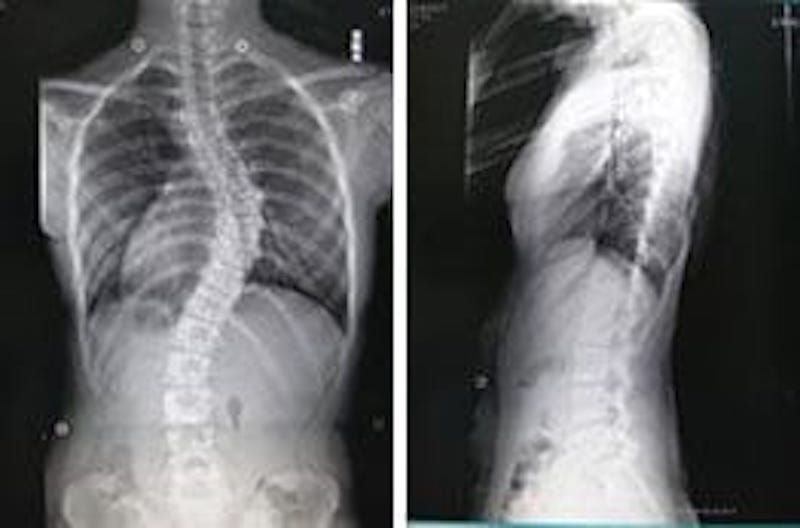

側弯症の種類と運動療法、ストレッチについてアレックス脊椎クリニック。

子供の側弯症について 側弯症外来 整形外科 │ 村山医療センタ。

側弯症の早期発見・評価の重要性 │ 村山医療センタ。

側弯症 脊椎・側弯症センター 国際医療福祉大学成田病院。